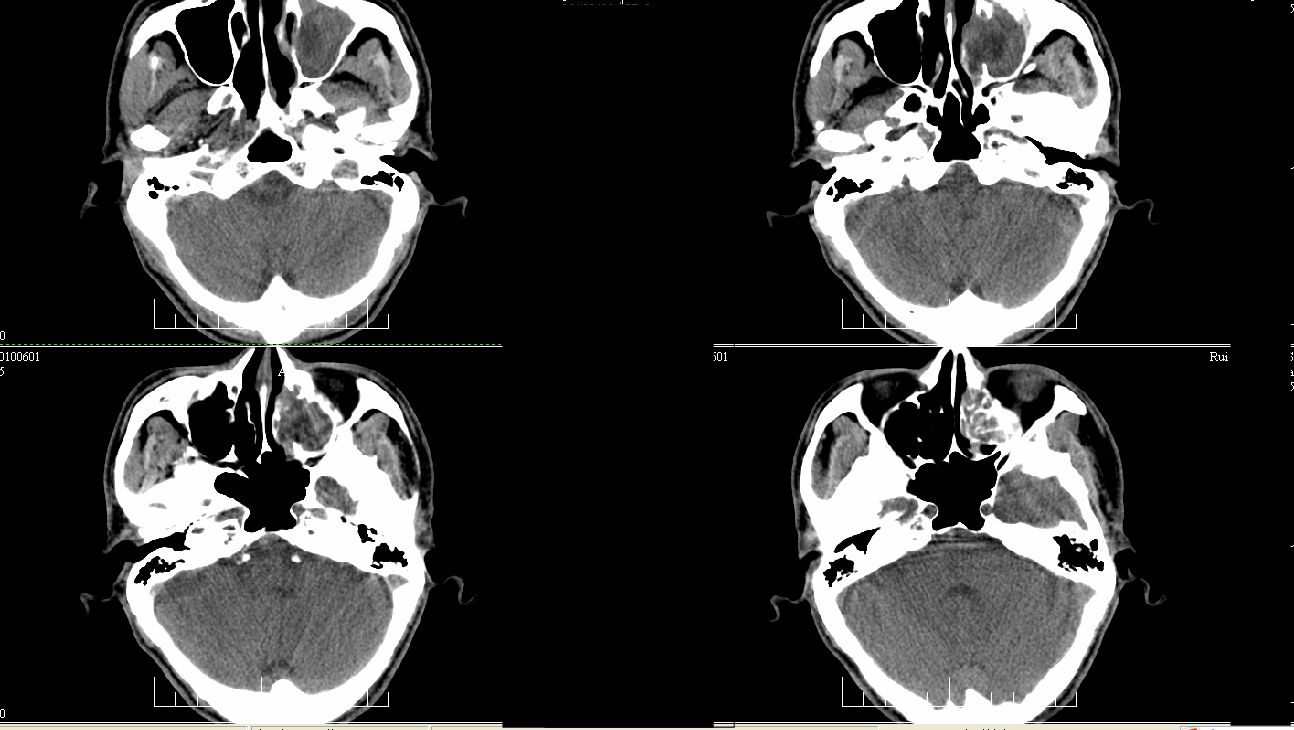

标题: CT26806:女,30岁,左侧面部疼痛10天,请会诊 [打印本页]

标题: CT26806:女,30岁,左侧面部疼痛10天,请会诊

我考虑霉菌性上颌窦、筛窦炎

左侧上颌窦及左侧筛窦炎症。

左侧上颌窦及左侧筛窦炎症。窦口扩大

左侧上颌窦内侧骨壁不完整,窦腔内可见软组织密度填充,内可见更低密度坏死区。不除外恶性,建议活检